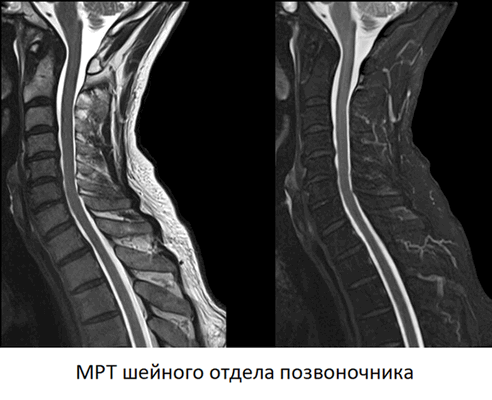

МРТ головы и шеи, что показывает

МРТ головы и шейного отдела позвоночника — метод диагностики болезней головного мозга и шеи. Процедура может проводиться в стандартном режиме, для исследования мягких тканей, или в ангио-режиме, для исследования кровеносных сосудов, кровоснабжающих центральную нервную систему. В основе метода — использование магнитных полей и радиоволн для получения послойных снимков области интереса с превосходной четкостью и детализацией.

Что показывает МРТ головы и шеи

Каждый МРТ снимок головы и шейного отдела позвоночника — это послойное изображение исследуемой области, сделанное в нескольких плоскостях. На нем четко различимы все анатомические структуры — головной и спинной мозг, нервы, кровеносные сосуды, мышцы, суставы и т.д. Метод позволяет сделать прижизненные снимки человеческого тела с высокой четкостью и самыми мельчайшими подробностями.

Расшифровывая снимки, врач-рентгенолог обращает внимание на малейшие признаки болезни. МРТ прекрасно “видит” воспаление, отек, нарушения кровообращения, опухоли и другие типовые патологические процессы. Это единственный на сегодняшний день метод, которые позволяет диагностировать практически все болезни головы и шейного отдела позвоночника за один раз.